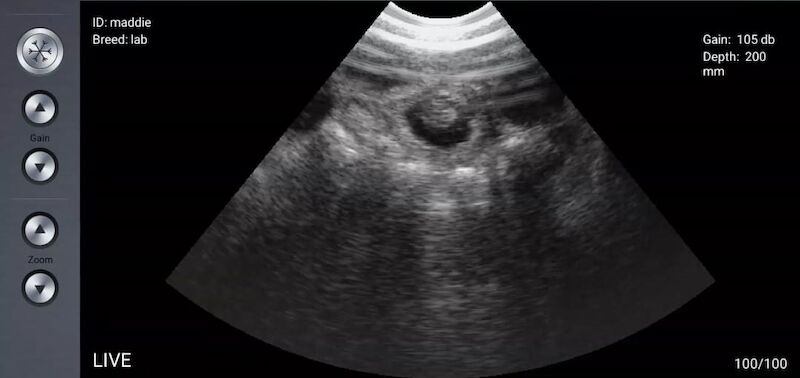

Abijax is a family run business and we have successfully been breeding the beautiful Labrador for over 20 years. We pride ourselves on our knowledge and experience within the Labrador which enables us to breed to a very high standard. All our pups are reared in our home with a lot of enrichment activities and care provided for all our dogs. We currently hold a 4 star breeders licence with our